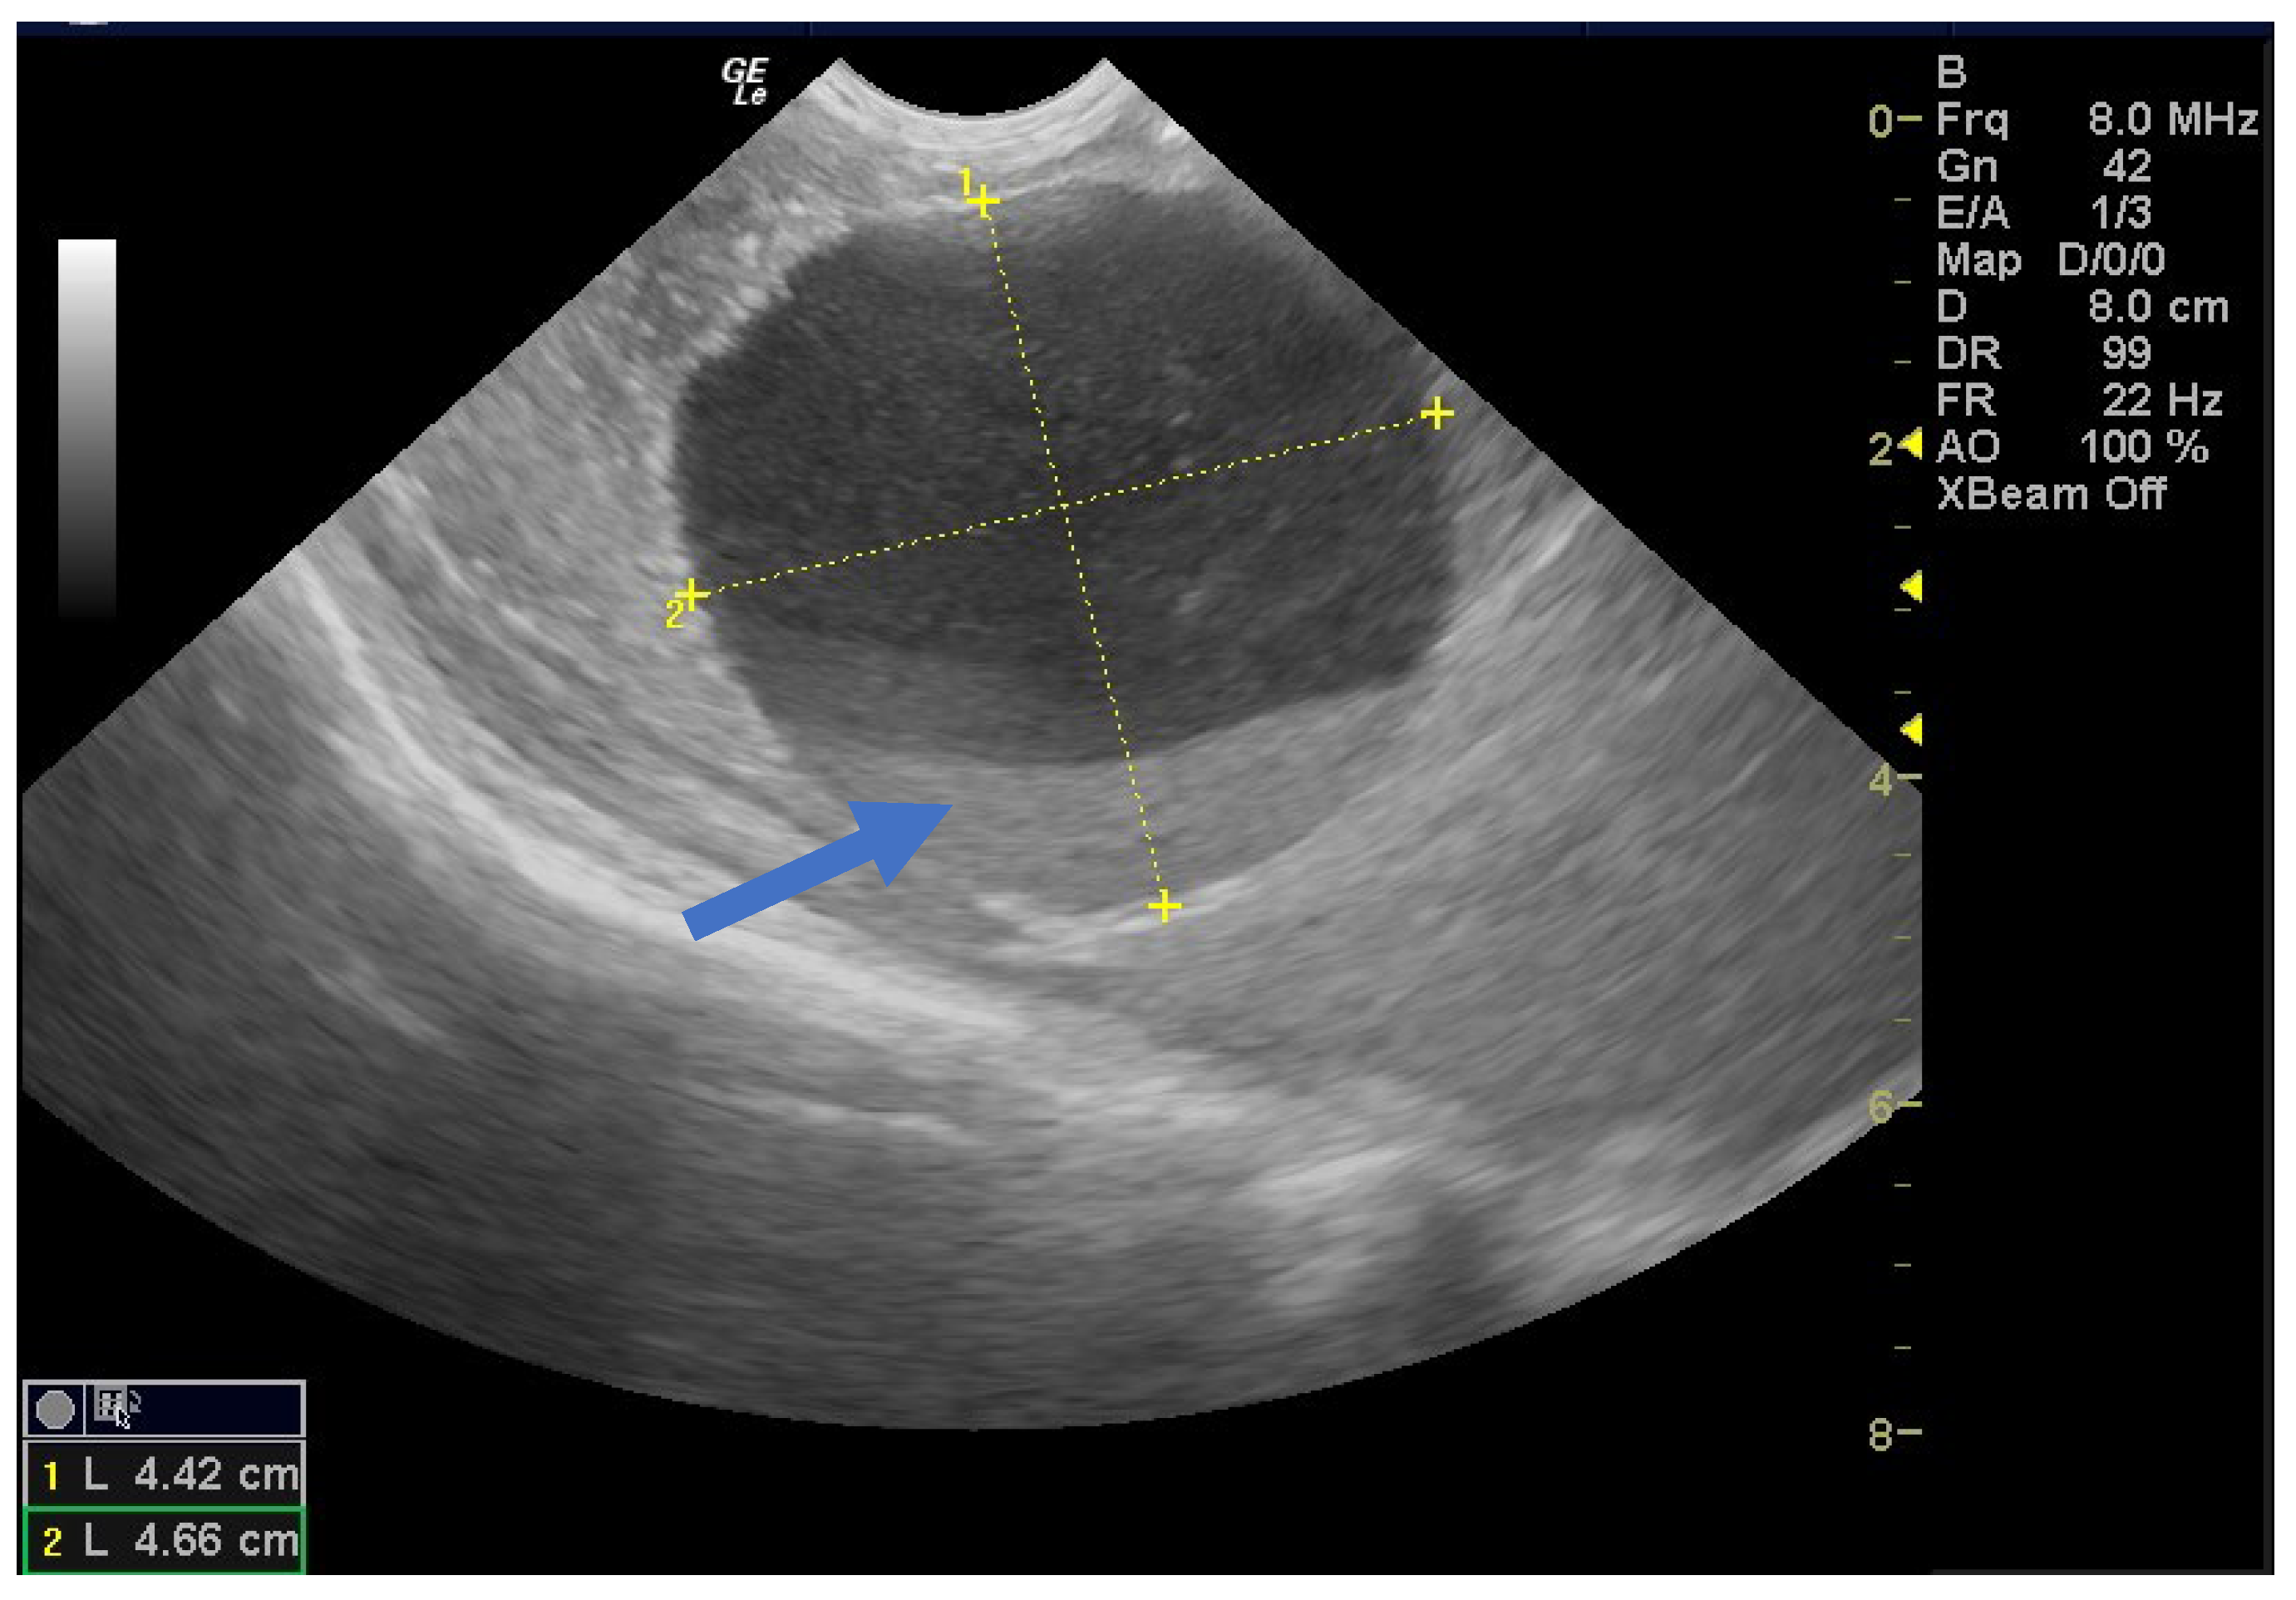

Of the nine simple cysts, seven regressed spontaneously within the first two months after birth (Figure 5 and Figure 6).

Figure 5.

Ultrasound image of a simple cyst with an intracystic blood clot (arrow) at the age of 2 weeks postpartum, which regressed spontaneously at 2 months.

Figure 6.

Ultrasound image of a neonatal simple cyst with a daughter cyst (blue arrow), which regressed spontaneously after 2 months.